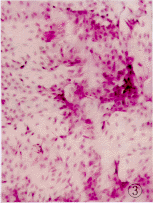

1级:结膜上皮细胞轻扩大,胞浆蓝绿色,N/C为1∶3,无角化,杯状细胞开始减少,密度下降,平均1个低倍视野下见7.4个杯状细胞。见图3、4所示。

图3 CIC分级1级(×100)